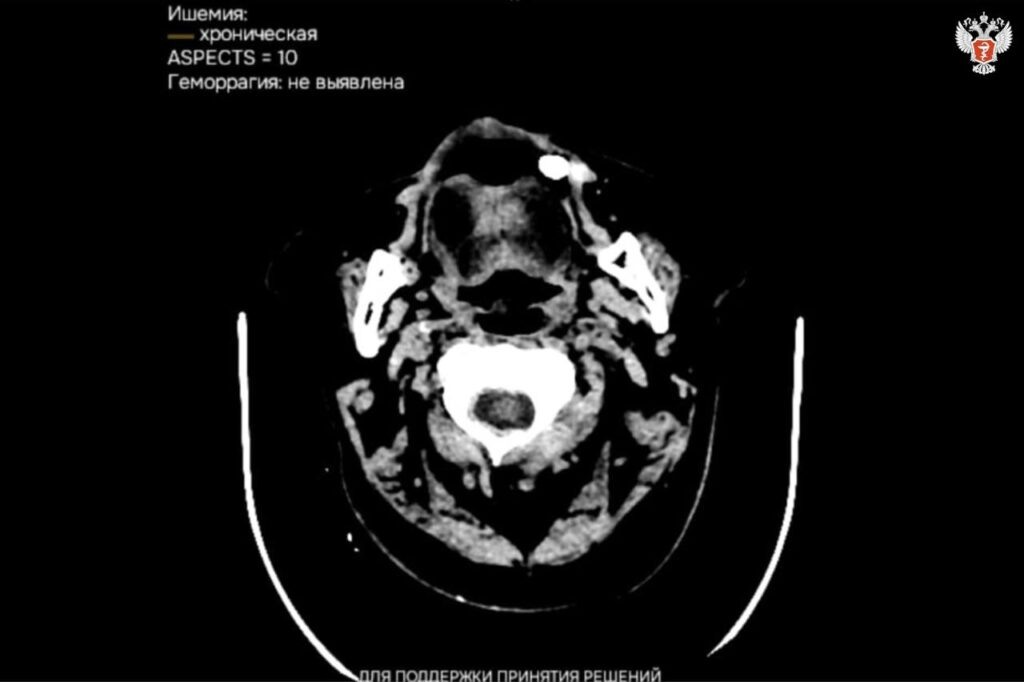

В медучреждениях Калмыкии внедряются сервисы с ИИ для расшифровки исследований

Искусственный интеллект анализирует любое исследование всего за 15 минут. На сегодняшний день с использованием ИИ обработано более 7 тыс. исследований, патологии выявили в более 3 тыс. случаях. Эти результаты свидетельствуют о высокой эффективности внедрения технологий в медицинскую практику, способствующих своевременному

обнаружению заболеваний и повышению точности диагностики. Отметим, что в декабре 2024 года медучреждения Калмыкии подключилась к платформе, объединяющей 17 сервисов для анализа КТ, рентгенографии, маммографии и флюорографии. В рамках проекта планируется до конца года обеспечить подключение всех медицинских организаций республики. Если Вам понравилась статья, просим поставить лайк и подписаться. Еще больше интересных и полезных статей вы можете прочитать - в нашем канале в Телеграм, и на сайте издательства "МЕДИК" medik.press. Будьте здоровы! Источник: Министерство здравоохранения Российской Федерации